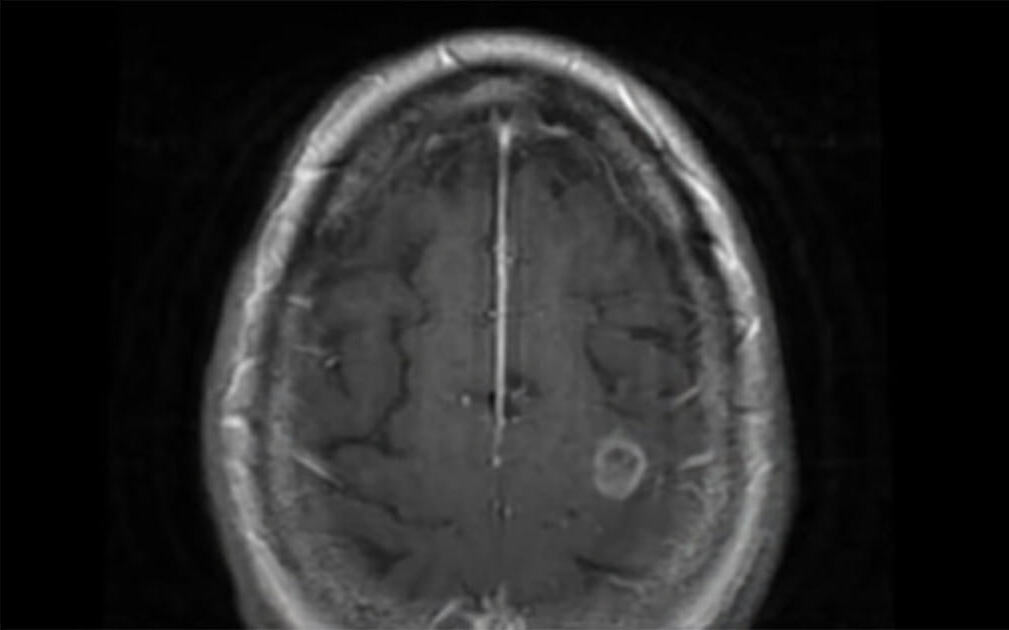

Seattle’ da yaşayan 69 yaşındaki bir kadın Aralık 2018’de öl-ümcül bir nöbet geçirdi. Nöbet geçirdiği esnada sağlık ekibi de zor anlar yaşadı. Beyin tümöründen şüphelenmişlerdi ancak gerçek ameliyat sırasında anlaşıldı. Ameliyatta kadından öl-übeyin dokusu çıkardılar.

69 yaşındaki kadının nöbet geçirmesine neden olan şeyin, sıcak toprakta ve suda yaşayan ve beyin hücrelerini aşamalı olarak öldürme yeteneğine sahip olan öl-ümcül bir amip olduğu anlaşıldı.

İsveç Tıp Merkezi’nde Doktor Charles Cobbs, “Patolog mikroskop altında bakarak ve karakteristiğini tespit etti… aslında dokudaki amip.” dedi.